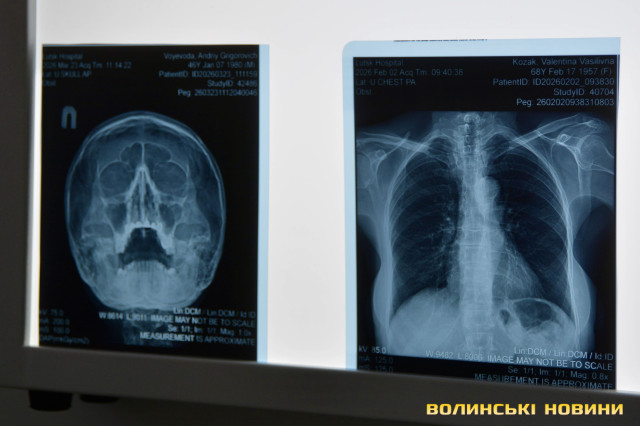

Щодо результатів обстеження в пересувному флюорографі, то, як прокоментувала Наталія Чурсіна, в більшості випадків у людей виявляють не туберкульоз, а інші патології. До слова, завдяки вбудованому штучному інтелекту таке обладнання швидко надає інформацію про наявні захворювання в людини, яка проходить обстеження.Рентгенологічне відділення